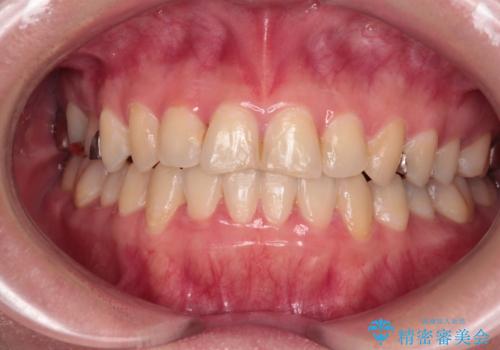

- 前歯のデコボコとクロスバイトを気にして来院された患者様です。

骨格的に下顎が前方位の受け口傾向であり、それが原因でクロスバイトとなっていました。

受け口傾向の非抜歯矯正であったため、インビザラインによる矯正治療をお勧めしましたが、自己管理が面倒であるとのことで、ワイヤー装置にて行うこととしました。

なお、右奥の歯が180度回転した状態で萌出しており、こちらは改善困難なため、そのままの向きで配列することとしました。